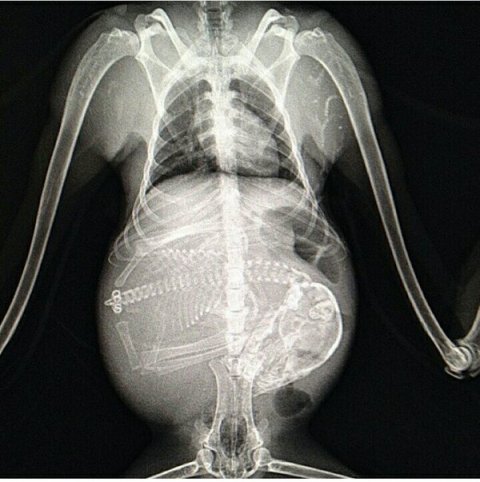

Մենք բոլորս լավ պատկերացնում ենք, թե ինչպես է անցնում մարդու հղիությունը, և շնորհիվ ժամանակակից տեխնոլոգիաների՝ կարող ենք տեսնել երեխային մայրիկի արգանդում հղիության ամենավաղ փուլում։ Իսկ ինչպե՞ս է ընթանում կենդանիների հղիությունը։ Մասնագետները, ովքեր հոգ են տանում հղի կենդանիների մասին, ներկայացրել են նրանց ռենտգենային և ուլտրաձայնային լուսանկարները, որոնք ձեր դատին է հանձնում «twizz.ru» կայքը։

Կապիկ